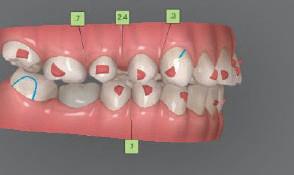

Цели на лечението и лечебен план Целите на лечението бяха следните: нивелиране и подреждане на зъбите и в двете зъбни дъги; отваряне на пространство за липсващия латерален резец; коригиране на отношенията при канините и моларите до клас I; и корекция на отклонението на срединната линия. Лечебният план включваше: корекция на отношенията при кучешките зъби и мола рите до клас I с дистализира не на максилата; отваряне на пространство в областта на #22 за поставя не на единичен имплант; корекция на срединната ли ния; и създаване на място за раз ширяване на зъб #12 и апрок симална редукция в долната челюст с цел подобряване на несъответствието по Болтън и осигуряване на подобра оклузия. Изпълнение на лечебния план Този случай бе изпълнен със системата за алайнери Invisalign (Align Technology). Одобреният първоначален лечебен план предвиждаше 49 алайне ра с дистализиране на задни те горни зъби до клас I (прибли зително с около 3.5 мм; фиг. 5). За бъдещия имплант в областта на липсващия латерал бе планирано пространство от 6.5 мм, докато във фронталния сегмент на долната челюст бе предвидена апроксимална редук ция. В дясната страна бутон за ластици клас II бе поставен на зъб #47 вместо на зъб #46, за да не се увреди короната на импланта. Понеже пациентката жи вееше в чужбина,

следните казуси: недобра оклу зия в дисталните зони по вре ме на дистализирането на гор ната челюст и накланяне на зъб #21 (фиг. 7). Последното се дължи на липсата на компози тен атачмънт на този зъб, каквото не бе зададено в пър Фиг. 4 Телерентгенография и цефалометричен анализ преди началото на лечението. Фиг. 5a–e Одобреният първоначален лечебен план. Фиг. 6a–h Снимки по време на лечението, показващи нуждата от внасяне на някои корекции. Фиг. 4 Фиг. 5a Фиг. 5d Фиг. 6a Фиг. 6d Фиг. 6f Фиг. 6b Фиг. 6e Фиг. 6g Фиг. 6h Фиг. 6c Фиг. 5e Фиг. 5b Фиг. 5c

Dental Tribune Bulgarian Edition / октомври 2022 г.18 воначалния план. Тези пробле ми бяха адресирани чрез допъл нителна поръчка на алайнери с торк контрол и зададено екст рудиране на задните зъби с цел установяване на добри оклузал ни контакти в дисталните об ласти, като бяха предвидени и оптимизирани атачмънти с контрол над корените за корекция на ангулацията на макси ларните резци (фиг. 8). Резултати от лечението Панорамната рентгено графия след ортодонтското лечение показа благоприятна паралелна позиция на съседни те зъби, подходяща за поставя не на имплант в областта на #22, както и конвергенция на ко рените на зъби #44 и 45 (фиг. 9), но преценихме, че няма да от деляме допълнително лечебно време за коригирането ѝ поради факта, че пациентката бе мно го доволна от постигнатия до момента резултат. След при ключване на лечението бяха постигнати отлични взаимо отношения клас I при мола рите и канините, а срединни

ти и клас II ластици е устано вено, че осигурява достатъч на дистализация без промяна на лицевата височина.23 Както се видя от цефалометричния анализ, точно това бе постиг нато и в представения случай като се има предвид, че лице вата височина остана същата като първоначалната. Предвид леката тенденция към дистал Фиг. 8a–e Поръчаните допълнителни алайнери. Фиг. 9 Панорамна рентгенография след края на лечението. Фиг. 10a–c Странични (а и с) и фронтална интраорални снимки след края на ортодонтското лечение и поставянето на импланта (b). Зъб #12 все още не беше протезиран. Фиг. 11а и b Оклузални снимки след ортодонтското лечение. Фиг. 7a Фиг. 8a Фиг. 7d Фиг. 8d Фиг. 9 Фиг. 10a Фиг. 10b Фиг. 10c Фиг. 11bФиг. 11a Фиг. 7b Фиг. 8b Фиг. 7e Фиг. 8e Фиг. 7c Фиг. 8c Фиг. 7a–e Интраоралната ситуация по време на лечението. клиничен случай с алайнери